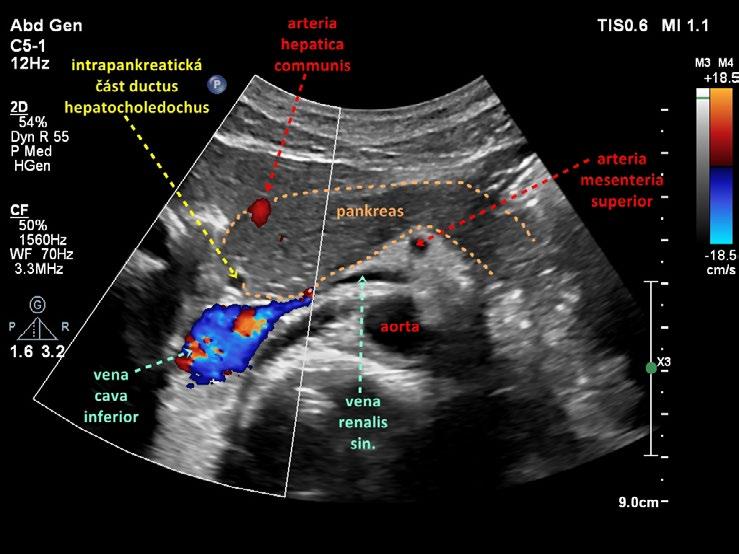

Obr. 1.24 Intrapankreatická část ductus hepatocholedochus

Obr. 1.26 Intrapankreatická část ductus hepatocholedochus podélně